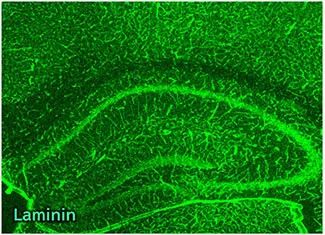

性能数据

物种:小鼠

部位:海马体

样品:冰冻切片

抗体浓度:1:500

数据提供:京都工艺纤维大学 应用生物学系 宮田老师